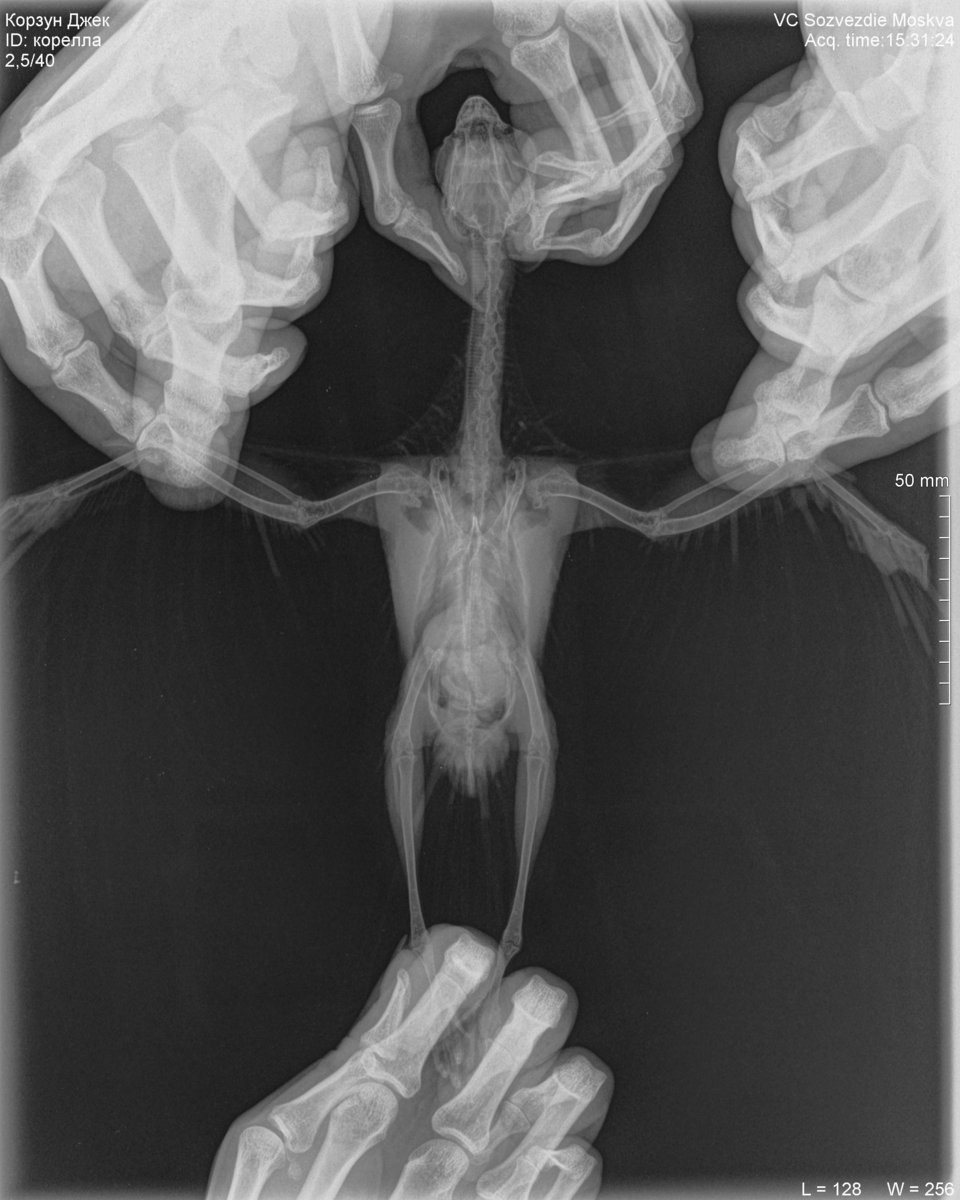

Здравствуйте! Лечу двух Гуленек - Оксаночку и Федорушку. Оксана у меня с конца июля. Лечили трихомоноз и микоплазму (не по анализам, а по симптомам, не сразу поняли, что это). Орнидазол 10 дней, пимафуцин на протяжении всего лечения + 4 дня, амоксиклав 10 дней, сумамед 14 дней. Все симптомы ушли во время лечения сумамедом. Изначально она попала ко мне с закисшими отёкшими глазками (пёрышки все были чистенькие) и слизью в горле, был запах от помёта (поэтому, возможно ошибочно, я и предположила трихомоноз) ,не всегда могла пищать, были приступы глотательных движений, во время которых слизь подступала к горлу и носу. Глазки стали проходить на амоксиклаве, но не до конца. На сумамеде всё ушло. Сейчас у Оксаночки,ттт, никаких симптомов нет. Федора у меня с 10 сентября, были наросты в горле, похожие на ранки, фото прилагаю, голоса не было, потом запах от помёта, лечила орнидазолом 14 дней, пимафуцин 14 дней. Думала голос восстанавливается, он стал лучше, но до конца не восстановился. Кроме того, когда полетает чуть больше чем пару тройку перелётов по комнате (когда мне ей лекарство надо дать, например) у неё отдышка. Дышит некоторое время с открытым клювом. Потом всё нормально, горлышко красное рыхлое. Периодически издаёт негромкий звук -пыф (как отрыжка).Бывало, кушает-кушает, потом шею вытягивает и некоторые зёрнышки вылетают. А по-началу вообще кушать трудно было ещё и из-за наростов, раздувалась вся. Наросты отпали, остальные симптомы до конца не прошли, поэтому поехали к доктору. Оксаночку даже брать не планировала, только в последний день решилась. В итоге ей, послушав обеих птиц, врач сделала рентген Оксаночке (фото прилагаю). У неё прослушались сухие хрипы с одной стороны, и жёсткое дыхание с другой. У Федоры жесткое дыхание с одной стороны, рентген не делали. Обеих пшикнули Фипристом 1 раз на кожу.Лечение тоже выписали одинаковое:1.Доксициклин (доксифин) 100мг растворить в 5мл воды,давать по 0,3мл (Оксаночке 0,28мл) внутрь - 2 раза в сутки,21 день2. Толтарокс 5% 0.15 мл (Оксане 0.14мл) внутрь 1 раз в сутки, 5 дней3.Дирофен 20 (паста или суспензия) 0,3мл внутрь, 1 раз в сутки, 3 дня4. Нистатин только Оксане прописали, но сказали, что и Федоре я могу его давать. Доктор сказала, что он транзитный, на печень не влияет,а пимафуцин не работает. На доксициклин у Оксаночки была реакция (видео прилагаю, если приложится). Спрыгнула слизь с кровью, это не симптом, такого не до не после (ттт) не было, а именно реакция на препарат. Его обеим поменяли да ципрофлоксацин. Таблетки 500мг, 1/2табл растворить в 6мл воды, 0,26 мл Оксане (она весит 280 грамм), 0,3мл Федоре (она весит 300 грамм), 2 раза в сутки Противопаразитарные на третий день (тоже обеим) отменили, т.к. Федорушку тошнило из-за них. В один из разов когда тошнило Федору, она тоже вытошлила немного слизи. Нистатин у нас не продаётся, даю Флуканозол. Капсула 50мл /5 мл воды, по 0,3 мл /2 раза в день. Сегодня 5й полный день приёма ципрофлоксацина. У Оксаночки восковица была белая до начала лечения, после доксициклина и реакции на него - порозовела. Сейчас чуть менее розовая, но не белая. Видимых симптомов у Оксаны как не было, так и нет. Федорочка «пыфает», при полётах отдышка ещё есть, но кушать стала не вытягивая шею, зерна не разбрасывает. Купила стетофонендоскоп, хочу следить за динамикой, ничего не смогла услышать. Не подскажете, как им пользоваться? Может я что-то не так делаю? Рентген у Оксаночки сильно нехороший? Ципрофлоксацин у нас дозировки в пределах нормы? Просто я по форумам полистала, везде гораздо ниже они. Сдавали пцр на микоплазму (в горветлаб спб), делали неделю, результат -у обеих нашли микоплазму. Да, у Оксаночки ещё переломы, но изначально она ко мне попала в таком состоянии, что не до них было, а потом они уже схватились.